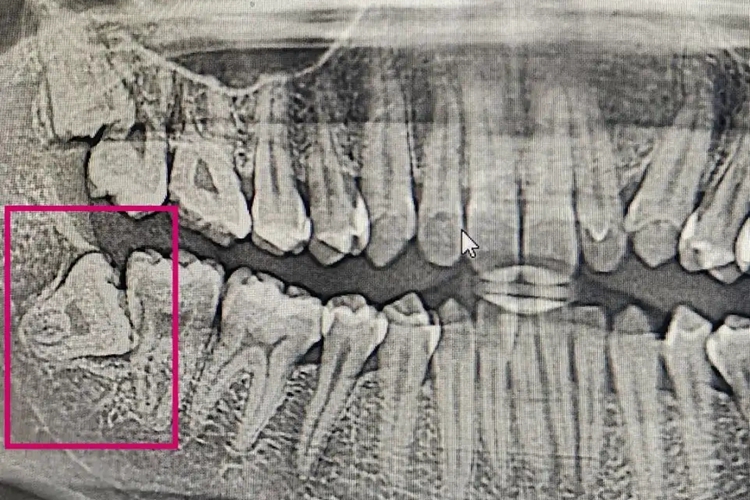

低位:对于低位阻生智齿,牙的最高部位低于第二磨牙的牙颈部。对于骨埋伏阻生,即牙全部被包埋于骨内现象,也属于低位阻生智齿。

一般情况下,下颌阻生智齿萌出至正常位置,形成良好咬合关系时,应尽量保留牙齿。出现红肿、疼痛等症状时,需积极进行拔出治疗。如高位阻生,多无冠部骨阻力,可去除邻牙阻力后拔除。而低位阻生,冠部骨阻力较大,需去除较多骨质,直至显露牙冠最大直径后方可拔除。